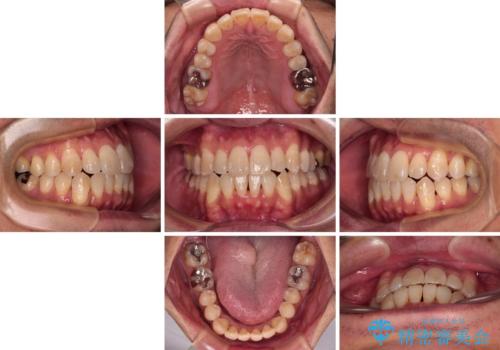

- 前歯のデコボコとクロスバイトを気にして来院された患者様です。

40代半ばであり、あまり周りに気を遣われずに治療を進めたいとのことで、インビザラインにて矯正治療を行うこととしました。

毎日22時間の装着時間をきっちりと守ってくださり、1年半かけずに思い通りの歯列に仕上げることができました。